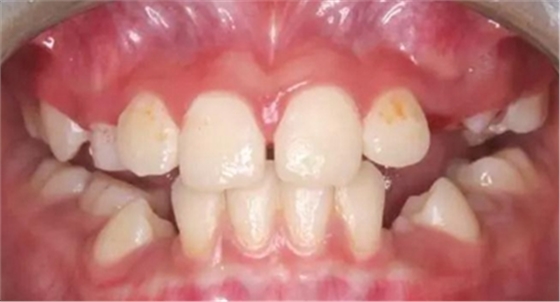

(1)檢查殆面及邊緣嵴的磨損情況,如發(fā)育溝是否存在,邊緣嵴有無變平,(牙合)面是否已經磨平,頰舌徑寬度如何等。

(2)鄰面接觸區(qū)情況,如接觸區(qū)有無增寬,頰舌側外展隙的寬度是否變小,鄰面接觸區(qū)是否已松離,或有鄰面齲存在等。

(3)對(牙合)牙有無充填式牙尖或尖銳邊緣嵴存在。

(4)牙列是否整齊,有無牙松動、移位、缺牙等情況。